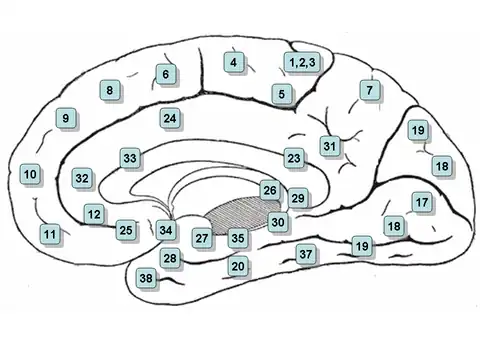

Medial surface of the brain with Brodmann's areas numbered. | |

Brodmann area 35, together with Brodmann area 36, comprise the perirhinal cortex. They are cytoarchitecturally defined temporal regions of the cerebral cortex.

This area is known as perirhinal area 35. It is a subdivision of the cytoarchitecturally defined hippocampal region of the cerebral cortex. In the human it is located along the rhinal sulcus. Cytoarchitectually it is bounded medially by the entorhinal area 28 and laterally by the ectorhinal area 36 (H).

With its medial boundary corresponding approximately to the rhinal sulcus it is located primarily in the fusiform gyrus. Cytoarchitecturally it is bounded laterally and caudally by the inferior temporal area 20, medially by the area 35 and rostrally by the temporopolar area 38 (H) (Brodmann-1909). Its function is part of the formation/consolidation and retrieval of declarative/hippocampal memory[1] amongst others for faces.[2]